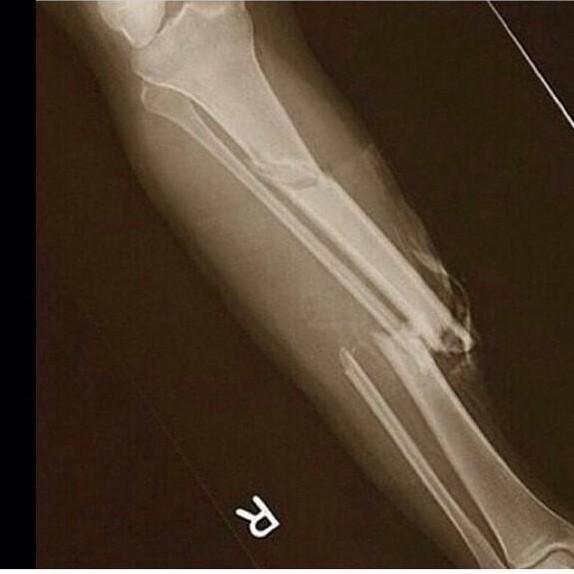

Paul George got his shtein all snapped up, there's no way he's playing this year

that was brutal

That's Theisman x2

http://deadspin.com/paul-george-breaks-his-leg-horrifically-in-team-usa-scr-1614935035

The fact he isn't screaming is amazing